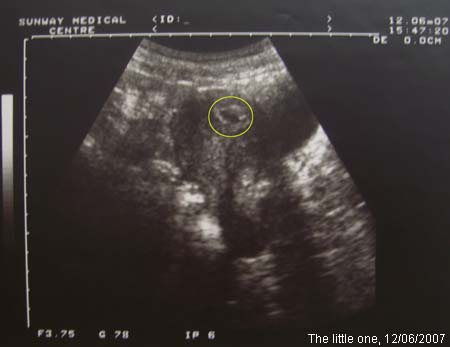

這是上兩個星期去看醫生時拍的。 圓圈中黑色的是裝胎兒的袋子,胎兒還沒有看到。